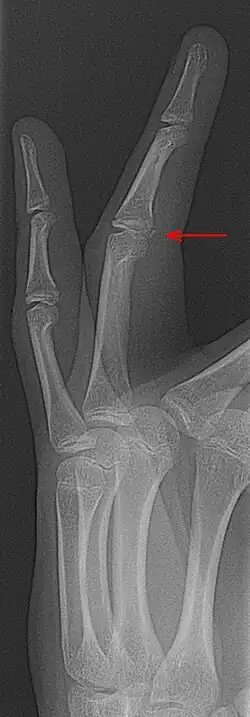

Fracture-avulsion

La « fracture-avulsion »[1] est une fracture avec déplacement de fragment osseux ou cartilagineux [2], l'os pouvant être arraché par une tension trop importante d'un ligament, par exemple au niveau du coude ou du genou (patella...)[3].